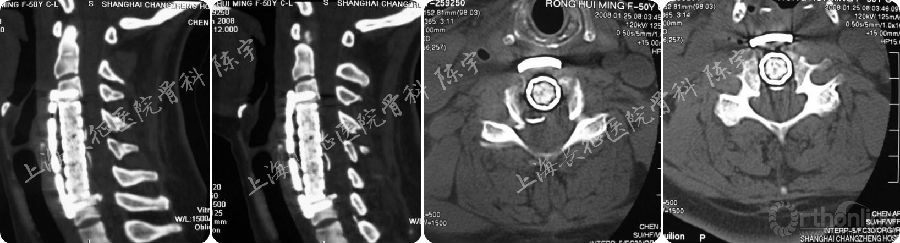

随访结果(5年):

随访第5年,患者神经功能完全恢复,JOA评分17分,颈前路钛网植骨融合,内固定位置良好,脊髓及硬膜囊形态进一步恢复,硬膜囊骨化进一步向前漂移并与前方植骨融合(图3A-G)。